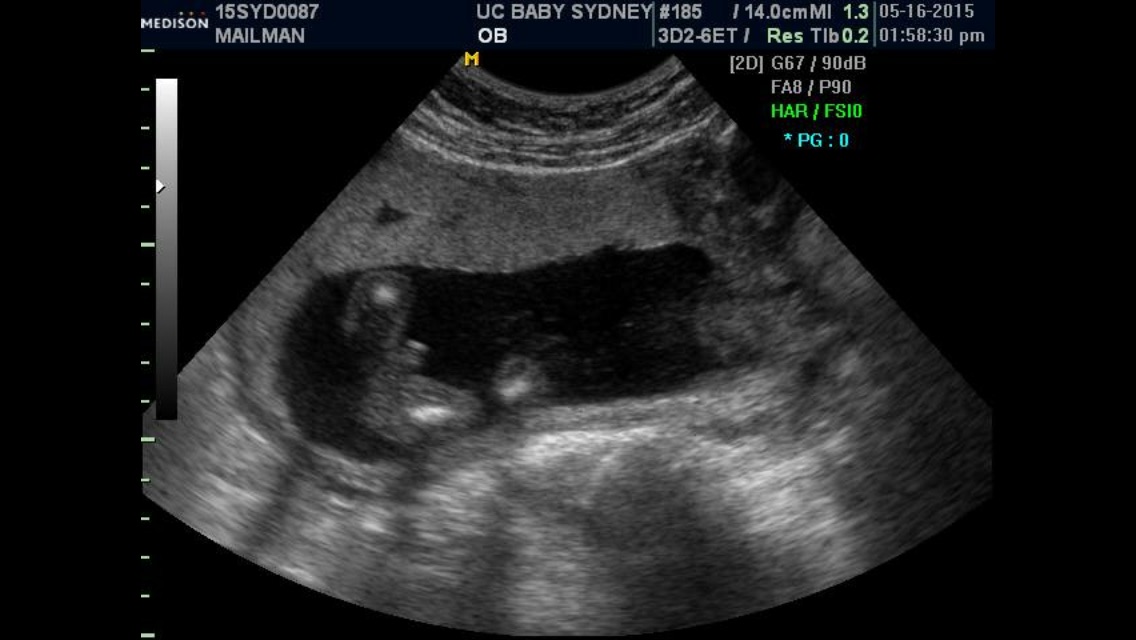

I am 20 weeks pregnant with my second child, and we excitedly opted to learn our babies gender through the SneakPeek test which revealed we are having a girl. I took the test when I was 13 weeks along. At my anatomy ultrasound yesterday, the tech revealed we are having a boy and this was also verified with a 2nd tech who has 30 years of experience and is known to be one of the best in my state at identifying gender through ultrasound.

• Boy parts are SUPER obvious on ultrasound. I had these done at 18w2d and he's clearly a BOY ! I would definately trust the ultrasound more then an at home blood test.